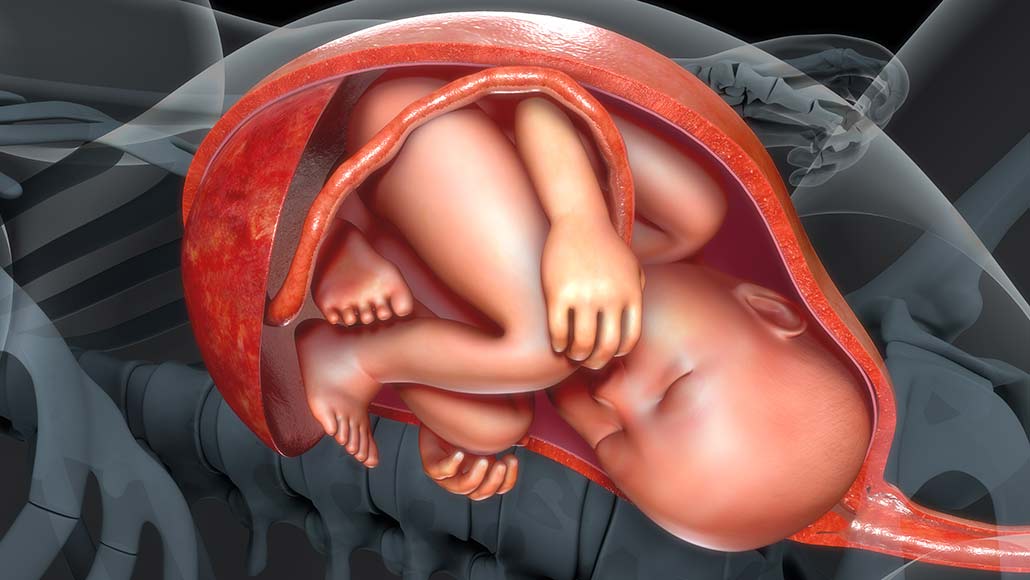

Oameni de știință din Italia au descoperit microplastice în placentele unor femei care au născut, catalogând situația „extrem de îngrijorătoare”.

O echipă de cercetători de la Spitalul Fatebenefratelli din Roma, specializat în pediatrie, și de la Universitatea Politecnica delle Marche au publicat un studiu în care au detaliat descoperirea, ca parte a unui experiment, a 12 fragmente microplastice în patru placente din șase donate de femei după nașterea copiilor lor.

Doar 3% din țesutulul din fiecare placentă a fost evaluat, ceea ce sugerează că numărul total al particulelor de microplastic ar putea fi mult mai mare.

Femeile care au participat la studiul din Italia nu au avut complicații la naștere, iar efectul particulelor minuscule de plastic este necunoscut. Cu toate acestea, experții au sugerat că materialele plastice ar putea fi o sursă de substanțe chimice dăunătoare care pot afecta imunitatea unui fetus în curs de dezvoltare.

„Prin prezența plasticului în organism, sistemul imunitar este perturbat, chiar și de ceea ce nu este organic. Este ca și cum ai avea un copil cyborg, care nu mai este alcătuit doar din celule umane, ci un amestec de entități biologice și anorganice”, au afirmat autorii studiului.